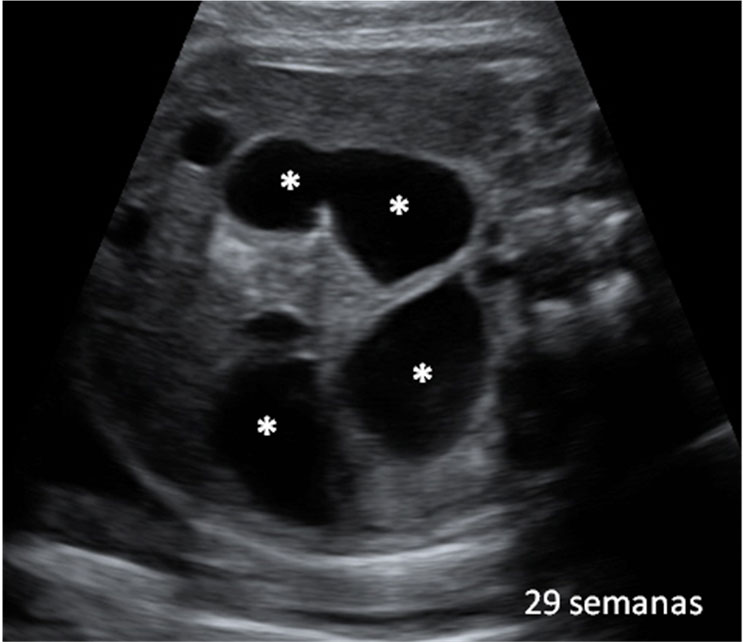

Las ecografías en 4D realizadas en la semana 20 de embarazo permiten ver el sexo femenino del feto con nitidez. En este caso, se ha capturado la imagen de los genitales femeninos, en concreto, la vulva.

En este ultrasonido, podemos ver la vulva del feto y otros pequeños detalles del sexo fetal.